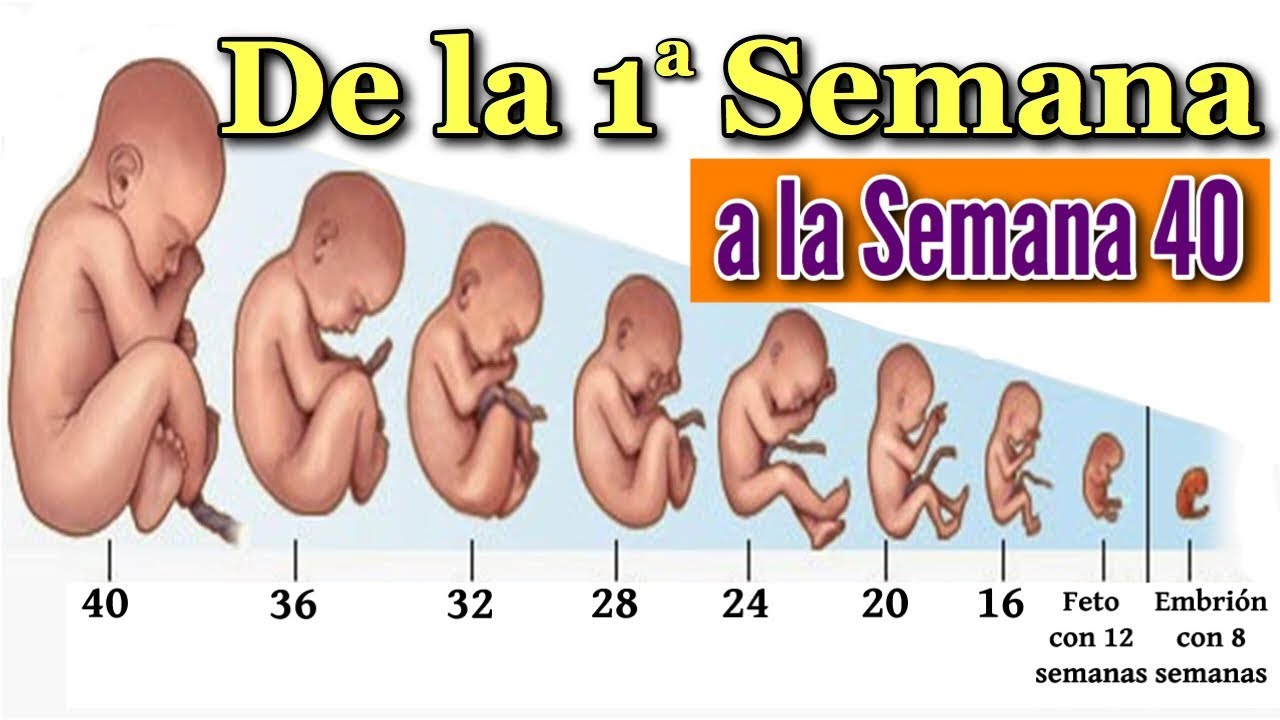

Desarrollo Del Feto Por Semanas

Publicidad. ¿Cuál es el tamaño de tu bebé dentro de tu barriga? Esta galería de fotos te muestra cómo va creciendo semana a semana de tu embarazo, comparando el tamaño de….

Desarrollo fetal: 16 semanas de embarazo. Revisión médica por Judith Venuti, Embrióloga. Escrito por Kate Marple. Tu bebé tiene esta semana el tamaño de un aguacate (palta). Mide unos 11,5 centímetros de largo (4,5 pulgadas) y pesa alrededor de 99 gramos (3 1/2 onzas). En las próximas tres semanas crecerá mucho, tanto que duplicará su.

Tu bebé la semana 16 mide alrededor de 11 cm y pesa 80 gramos (1) . Está totalmente cubierto por un vello fino, el lanugo, empezando a tenerlo en cejas y labio superior, lo que humaniza su apariencia. Comienza a desarrollar las uñas de manos y pies. Sus piernas se alargan respecto a los brazos, estirándose y doblándose por las rodillas y.

El feto mide entre 10,8 a 11,6 centímetros y pesa 80 gramos en la semana 16 de embarazo. Todo su cuerpo, incluida su cabeza, está recubierto de ese pelo tan fino, el lanugo, pero su apariencia se humaniza en esta fase de su desarrollo. Las primeras zonas en las que el bebé empieza a tener pelo son las cejas y sobre el labio superior.Tras el nacimiento, este pelo se cae y empieza a crecer.